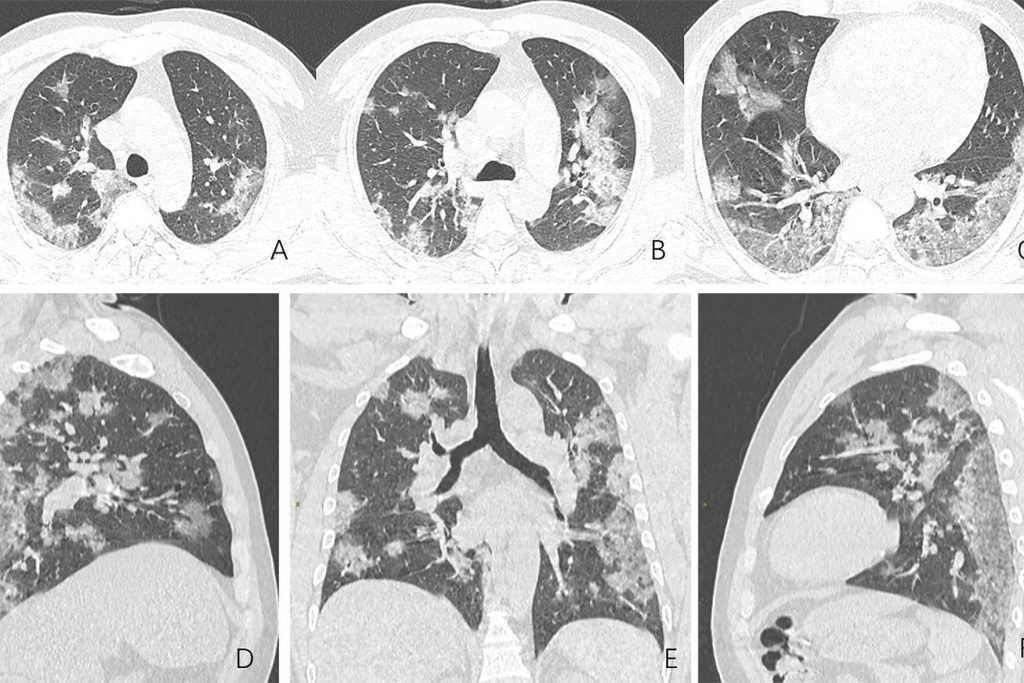

Объективно судить о том, что человек страдает тяжелой формой коронавируса позволяет томография легких. На снимках видно, что более половины площади органа поражено (возникает эффект матового стекла).

Пневмония при тяжелой форме

Коронавирусная пневмония отличается от обычного воспаления легких при бактериальной или вирусной инфекции. Это — пневмонит, при котором страдает интерстициальная ткань легких, а в мелкие сосуды, питающие их, закупориваются тромбами.

О развитии пневмонита при коронавирусе может свидетельствовать высокая температура тела дольше 4-5 дней, сильная одышка, когда человек находится в покое. Болезнь также сопровождается мучительными приступами кашля, головными болями и слабостью.